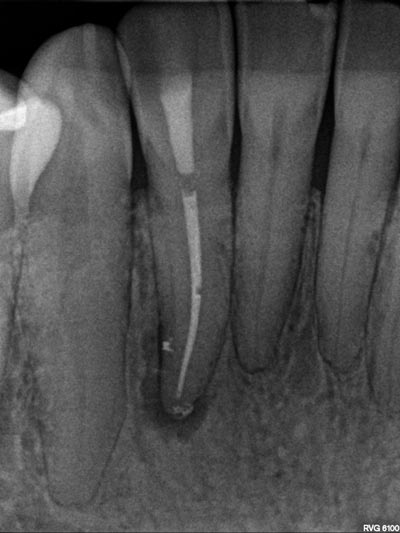

Imágenes: Endodoncia en un incisivo inferior calcificado y necrótico.